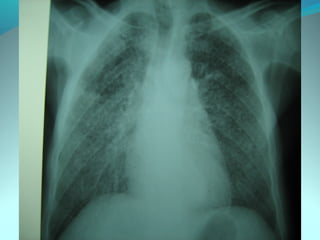

Cliché normal